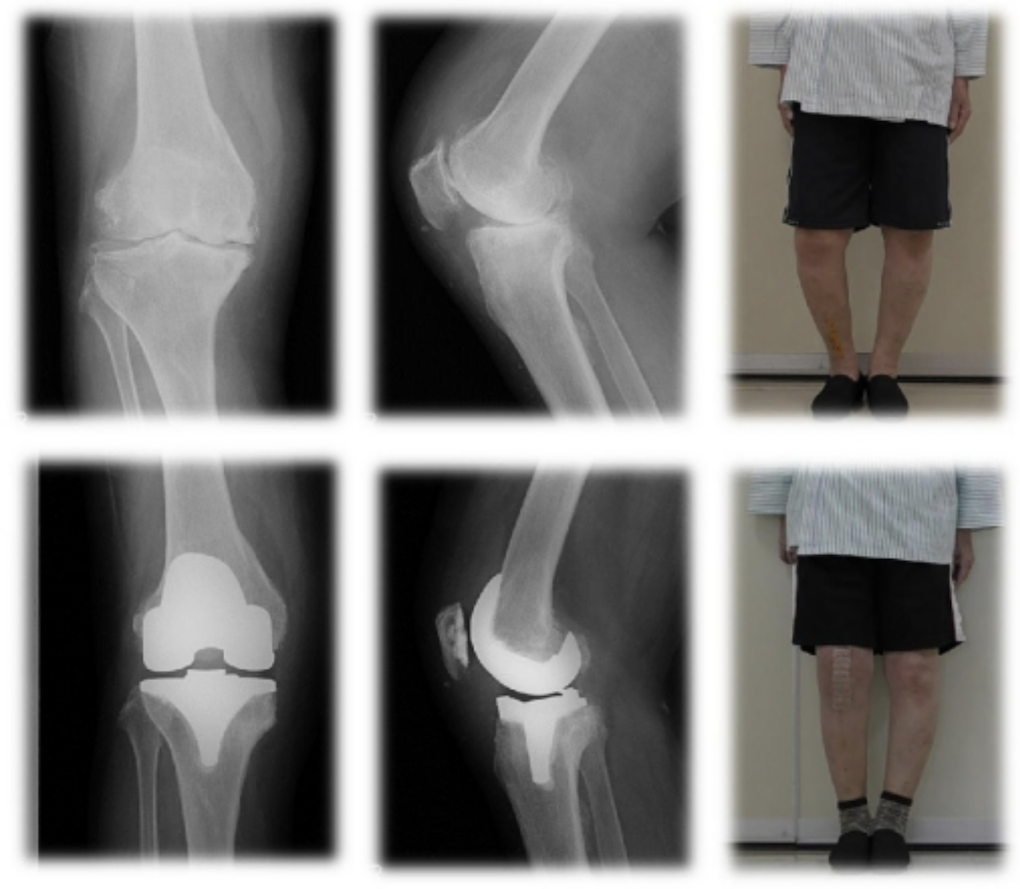

人工膝関節置換術(Total Knee Arthroplasty)

傷ついてしまった膝の表面の軟骨や骨を切り取り、膝の変形を矯正し、金属やセラミック、ポリエチレンなどででできた人工関節に置き換える手術です。変形が高度な変形性膝関節症の方やリウマチの方が適応になります。